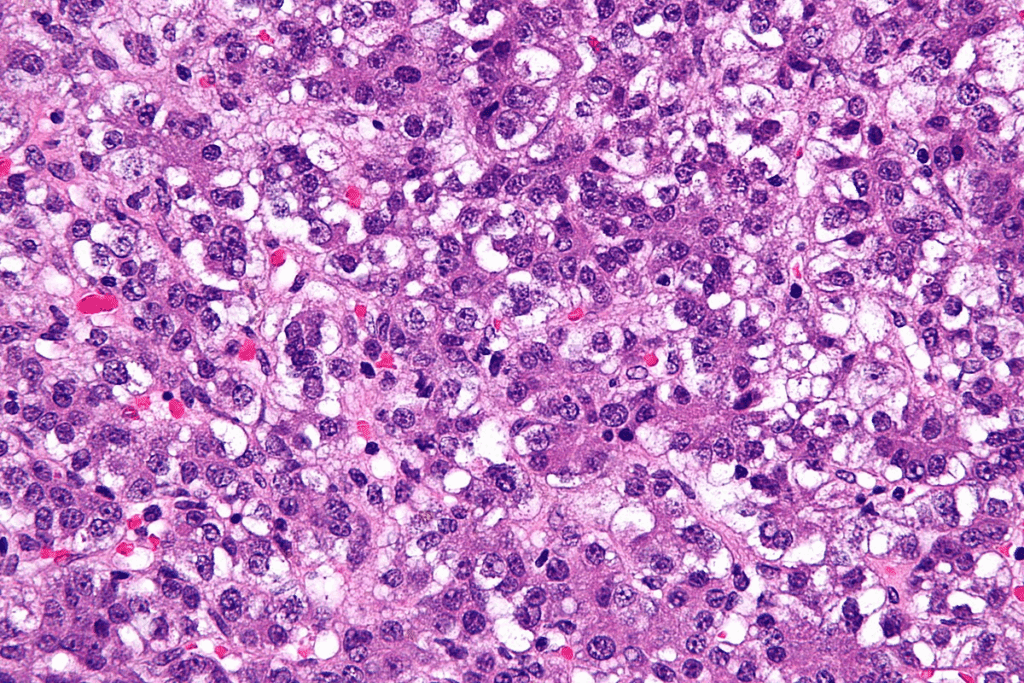

Stage1 Hepatoblastoma: Defining Characteristics

Stage1 hepatoblastoma is a type of liver cancer that can be fully removed by surgery. It is in its early stages, which means it’s easier to treat. This stage is very important for choosing the right treatment and has a better chance of success compared to later stages.

Complete Resection with Clear Margins

A key feature of Stage1 hepatoblastoma is the ability to remove the tumor completely. This means all cancer cells are taken out, leaving no trace behind. Having clear margins is key to preventing the cancer from coming back and improving survival chances.

Tumor Confined to Liver Segments

In Stage1 hepatoblastoma, the tumor stays within one or more liver segments. This makes it easier to remove surgically. When the tumor is in specific liver areas, doctors can plan and perform the surgery more easily.

Absence of Metastasis or Vascular Invasion

Another key feature of Stage1 hepatoblastoma is that it hasn’t spread to other parts of the body. There’s no sign of cancer cells in the blood vessels. This is a good sign and helps doctors focus their treatment.